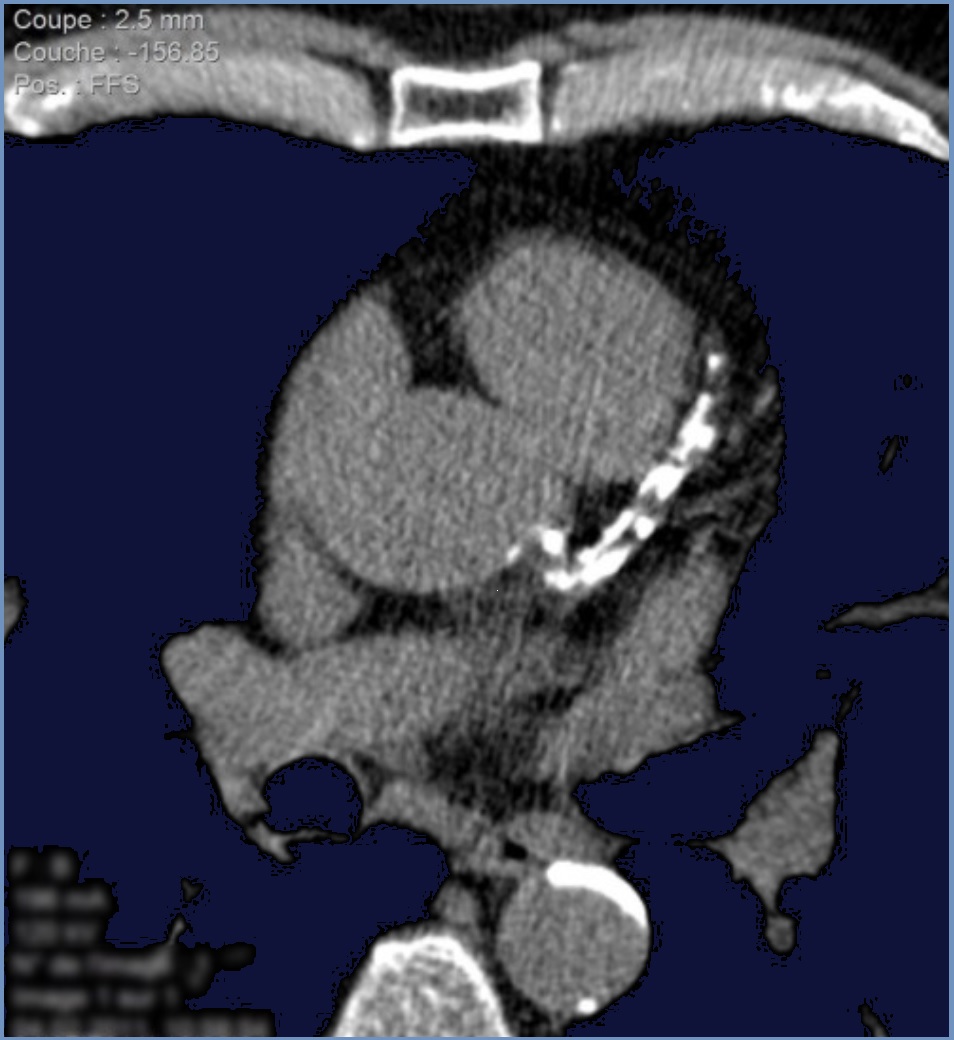

L'examen de score calcique coronaire calcule la quantité de plaque calcifiée dans les artères. Ces calcifications constituent un indice précoce de maladie du cœur. Votre professionnel de la santé peut prescrire ce test de diagnostic dans le but de vérifier si vous présentez un risque plus élevé de développer des problèmes cardiaques.. De détecter des calcifications des artères coronaires ou des valves cardiaques, avec établissement du score calcique qui peut être un critère pronostic. D'identifier des calcifications péricardiques; L'évaluation de la fonction cardiaque (cœur droit et gauche) De visualiser l'anatomie du cœur, de ses différentes cavités pour un contrôle